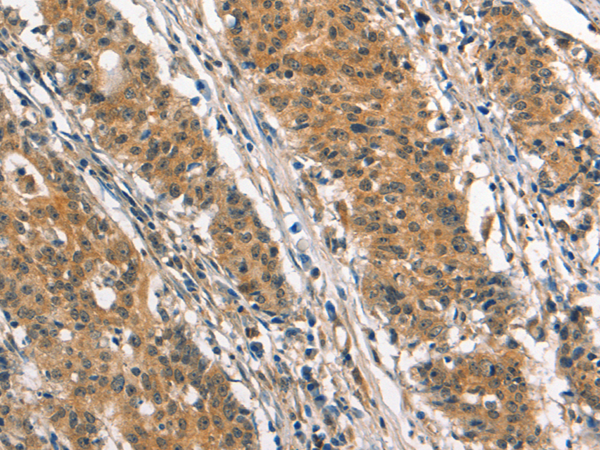

分类: 科研抗体货号: P04704别名: ASB; G4S; MPS6应用: WB,IHC反应种属: Human